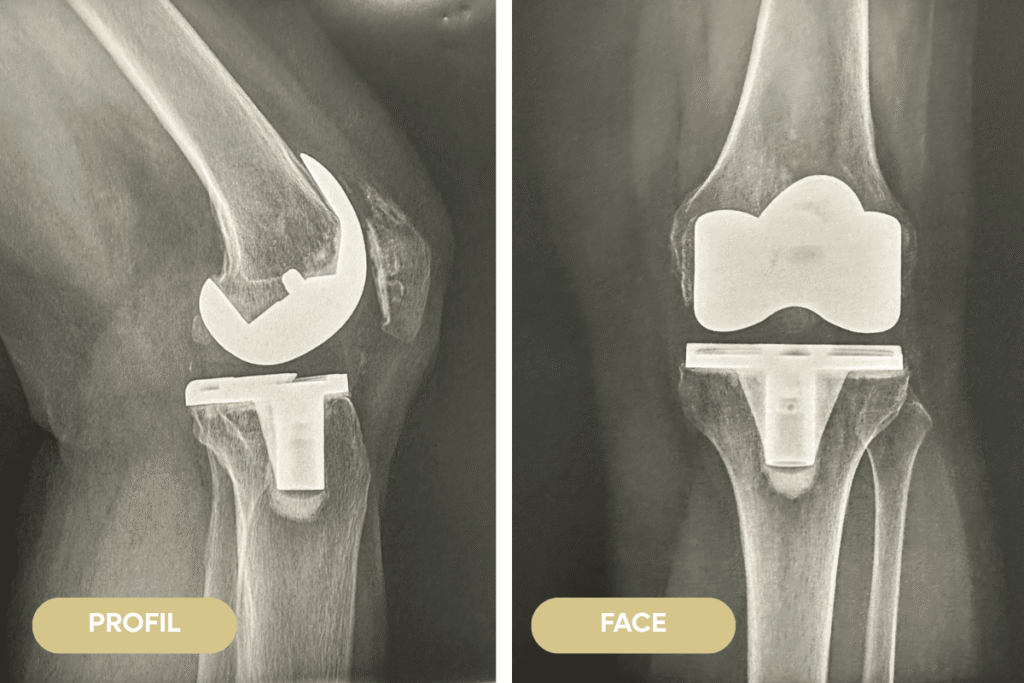

Mise en place d’une prothèse totale du genou après l’échec de nombreux traitements

Patient de 72 ans présentant une gonarthrose sévère, invalidante, avec diminution du périmètre de marche, douleur quotidienne, insomniante et hanche. Échec de tous les traitements conservateurs de type rééducation, semelles orthopédiques et infiltrations. Après une longue discussion avec le patient, nous optons pour la mise en place d’une prothèse totale de genou.